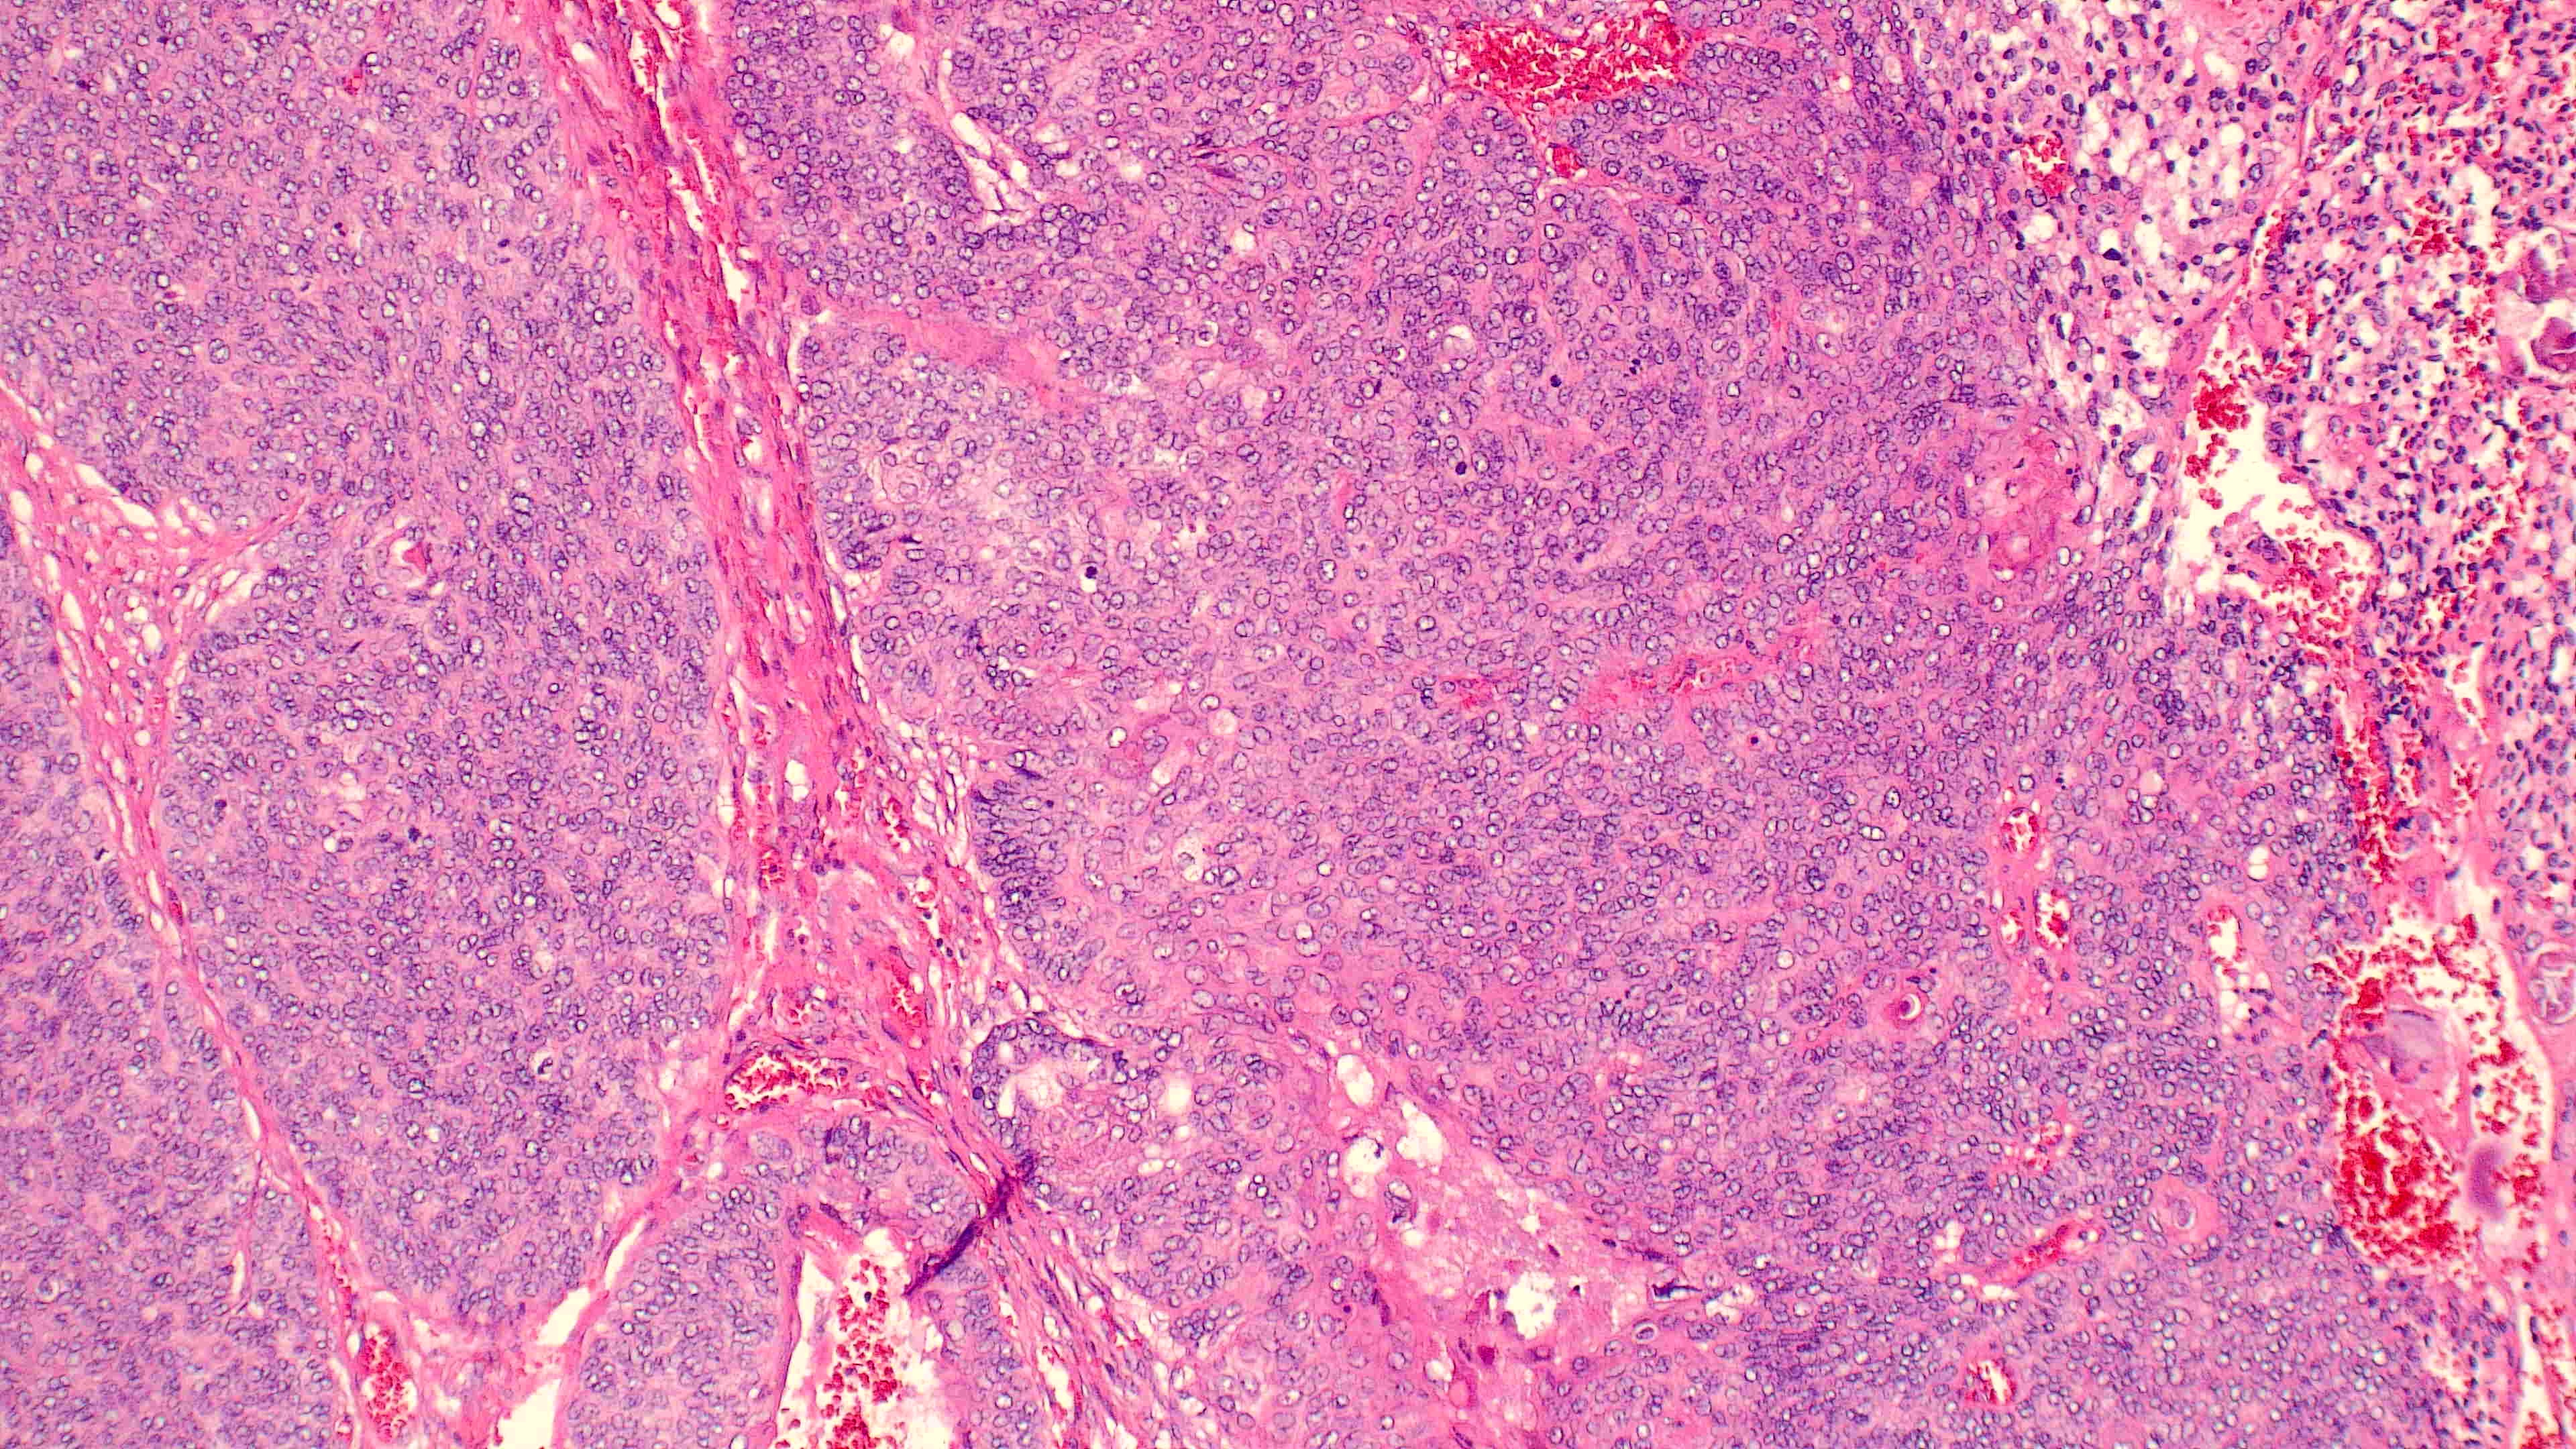

下巴肿物

性别

男

年龄

70岁

临床诊断

一般病史

0

标本名称

大体所见

带皮不规则组织3*3*2cm,切面灰白灰褐实性质软

1.考虑:来自汗腺;2.恶性?

会诊结果:小汗腺汗孔癌